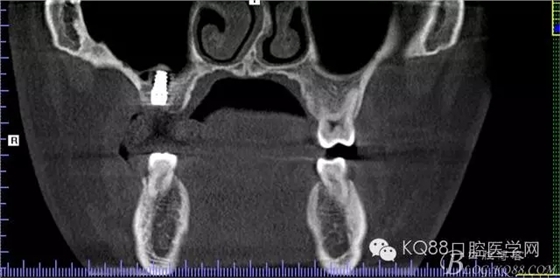

植入后,CBCT

另外一個(gè)切面。竇底粘膜完整連續(xù)。可以看到上下咬合的位置關(guān)系。